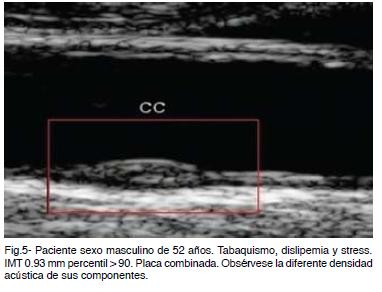

La presencia de placa siempre significa aterosclerosis. Estas son clasificadas de acuerdo al grado de estenosis y su morfoestructura. Un compromiso obstructivo de 50 % o mayor indica riesgo CV elevado.

De acuerdo a su morfoestructura se clasifican en duras, combinadas y blandas (Figura 4 y Figura 5). Un punto esencial es definir lo que se denomina placa vulnerable.

Placa vulnerable es aquella de rápida evolución y alta probabilidad de ruptura y trombosis configurando un estado inestable de alto riesgo y precursor de complicaciones. Su ruptura se produce por un proceso inflamatorio inmunomediado con liberación de enzimas proteolíticas y por factores hemodinámicos con un incremento anormal del shear stress oscilatorio. Son placas heterogéneas de cubierta fina, irregular, con alto contenido lipídico (ecolucente), nódulos cálcicos próximos a la cubierta de la placa, hemorragia intraplaca (ecolucente), remodelación expansiva y posible ulceración (Figura 6).